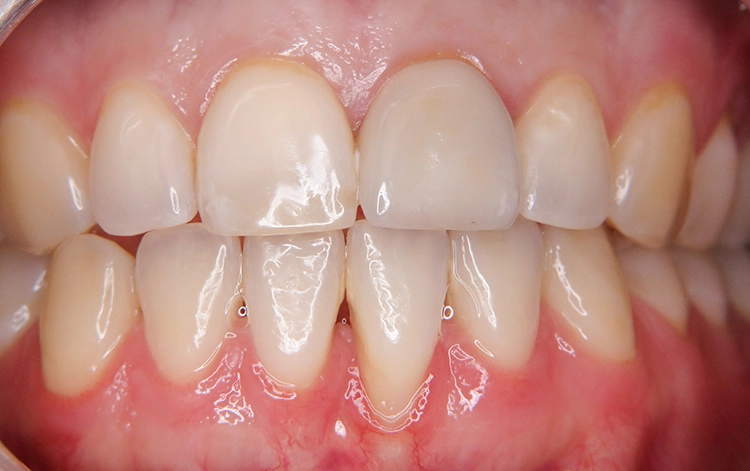

Die junge Patientin konsultierte die Zahnarztpraxis mit Beschwerden am Zahn 21. Der endodontisch vorbehandelte Zahn (multiple Wurzelspitzenresektionen) war mit einer Krone prothetisch versorgt (Abb. 1). Die Krone wirkte im Mund etwas dunkel und hatte einen grauen Schimmer. Da der Zahn zudem immer wieder Beschwerden bereitete, äußerte die Patientin den Wunsch nach einer Neuversorgung. Ansonsten war sie vollbezahnt und funktionell ohne pathologischen Befund. Parodontal zeigte sich eine kleine Rezession im Unterkiefer-Frontzahnbereich.